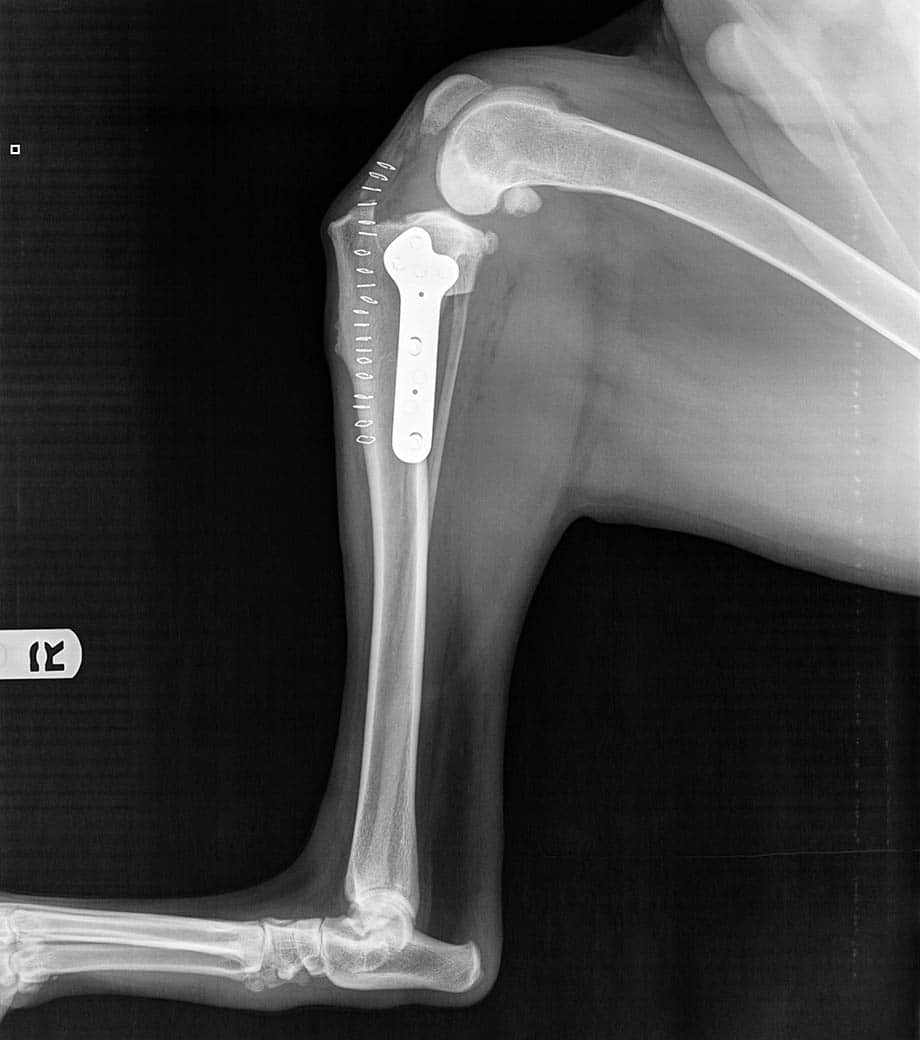

Cranial Cruciate Ligament Disease

Surgical repair to restore stability and comfort in unstable knees.

Patella (Kneecap) Luxation

Corrective surgery to realign the kneecap and improve mobility.